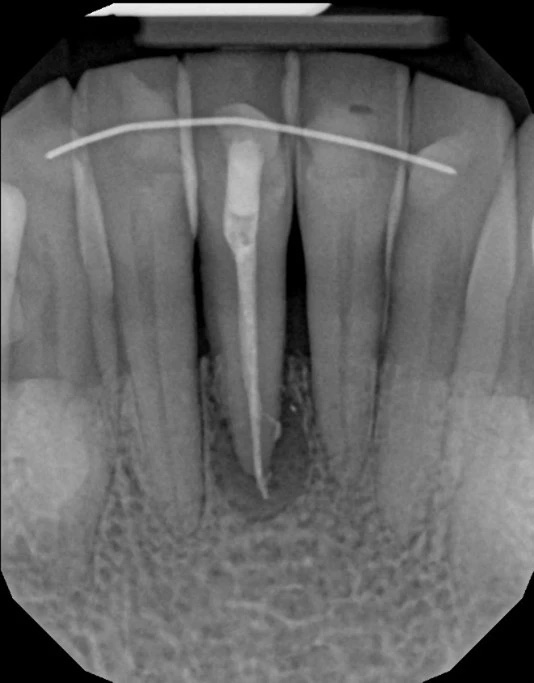

Symptoms that may prompt evaluation include lingering or recurrent pain, swelling, a draining sinus tract, or radiographic evidence of a radiolucency at the root apex. However, some troublesome lesions are discovered incidentally on routine imaging; lack of symptoms does not always mean absence of disease. Advanced imaging such as cone beam CT (CBCT) provides a three-dimensional view that helps clinicians determine whether apicoectomy is technically feasible and likely to be successful.

Cone beam CT provides a three-dimensional view of the tooth, surrounding bone, and nearby anatomical structures, enabling more precise diagnosis and surgical planning. CBCT can reveal canal morphology, root fractures, the extent of periapical lesions, and relationships to critical structures such as sinuses or nerves. This detailed information helps clinicians assess whether a retrograde approach is feasible and what surgical access will be required.

Using CBCT reduces uncertainty during case selection and supports microsurgical strategies that minimize bone removal and protect adjacent anatomy. The technology improves communication with patients by showing the problem in three dimensions and explaining why a particular course of care is recommended. Ultimately, CBCT contributes to more predictable outcomes and tailored treatment plans.